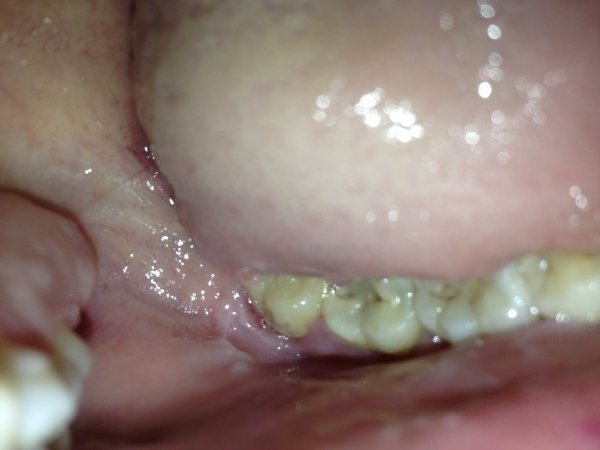

Лезет зуб мудрости, точнее два, сверху и снизу на одной стороне, но возможность увидеть и показать, если только снизу.

Что делать? Я так понял, там воспаление началось, больно глотать и открывать рот, порой. Есть также небольшие ранки возле, над зубом и на десне справа. Можно ли его не рвать?